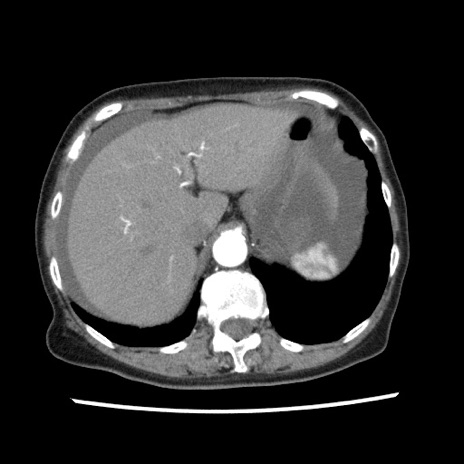

症例1(横断像)

【症例】80歳代女性

【主訴】腹痛

【現病歴】8時間前から腹痛あり来院。

【既往歴】糖尿病、脂質異常症、子宮体癌にて子宮全摘術

【身体所見】意識清明・会話良好だが腹痛で苦悶様、全腹部にわたって反跳痛と圧痛あり

【データ】WBC 13600、CRP 0.14、LDH 224、CK 90